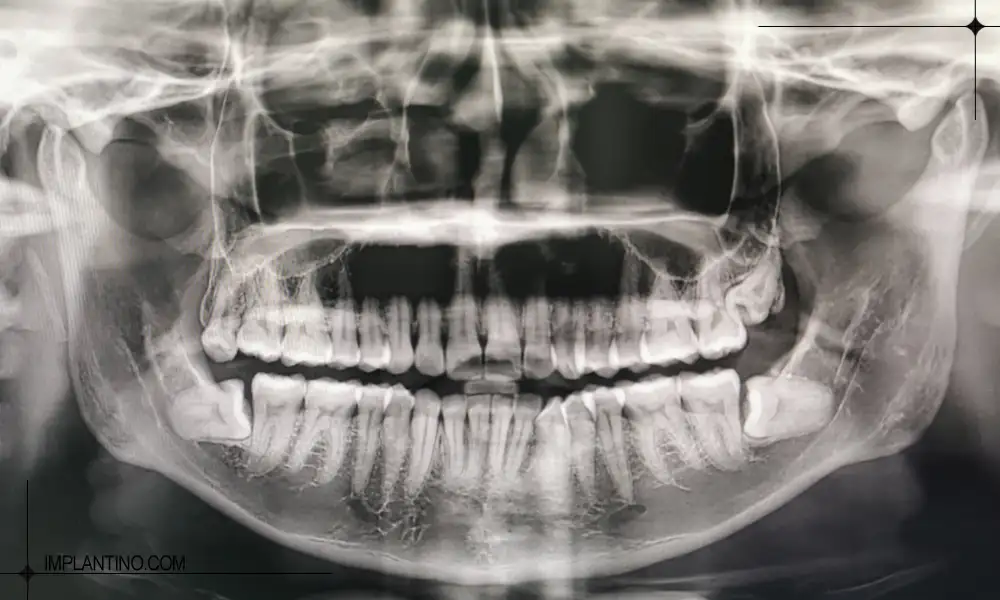

عکس opg چیست؟

OPG که مخفف Orthopantomogram است، یک نوع رادیوگرافی پانورامیک محسوب می شود که تصویری دو بعدی از کل فک بالا و پایین، دندان ها و بافت های اطراف آن ارائه می دهد. برخلاف رادیوگرافی تک دندان، OPG دید کلی و یکپارچه ای از دهان فراهم می کند و برای تشخیص مشکلات گسترده تر، برنامه ریزی درمان های پیچیده و پایش وضعیت دندان ها و فک بسیار کاربرد دارد.